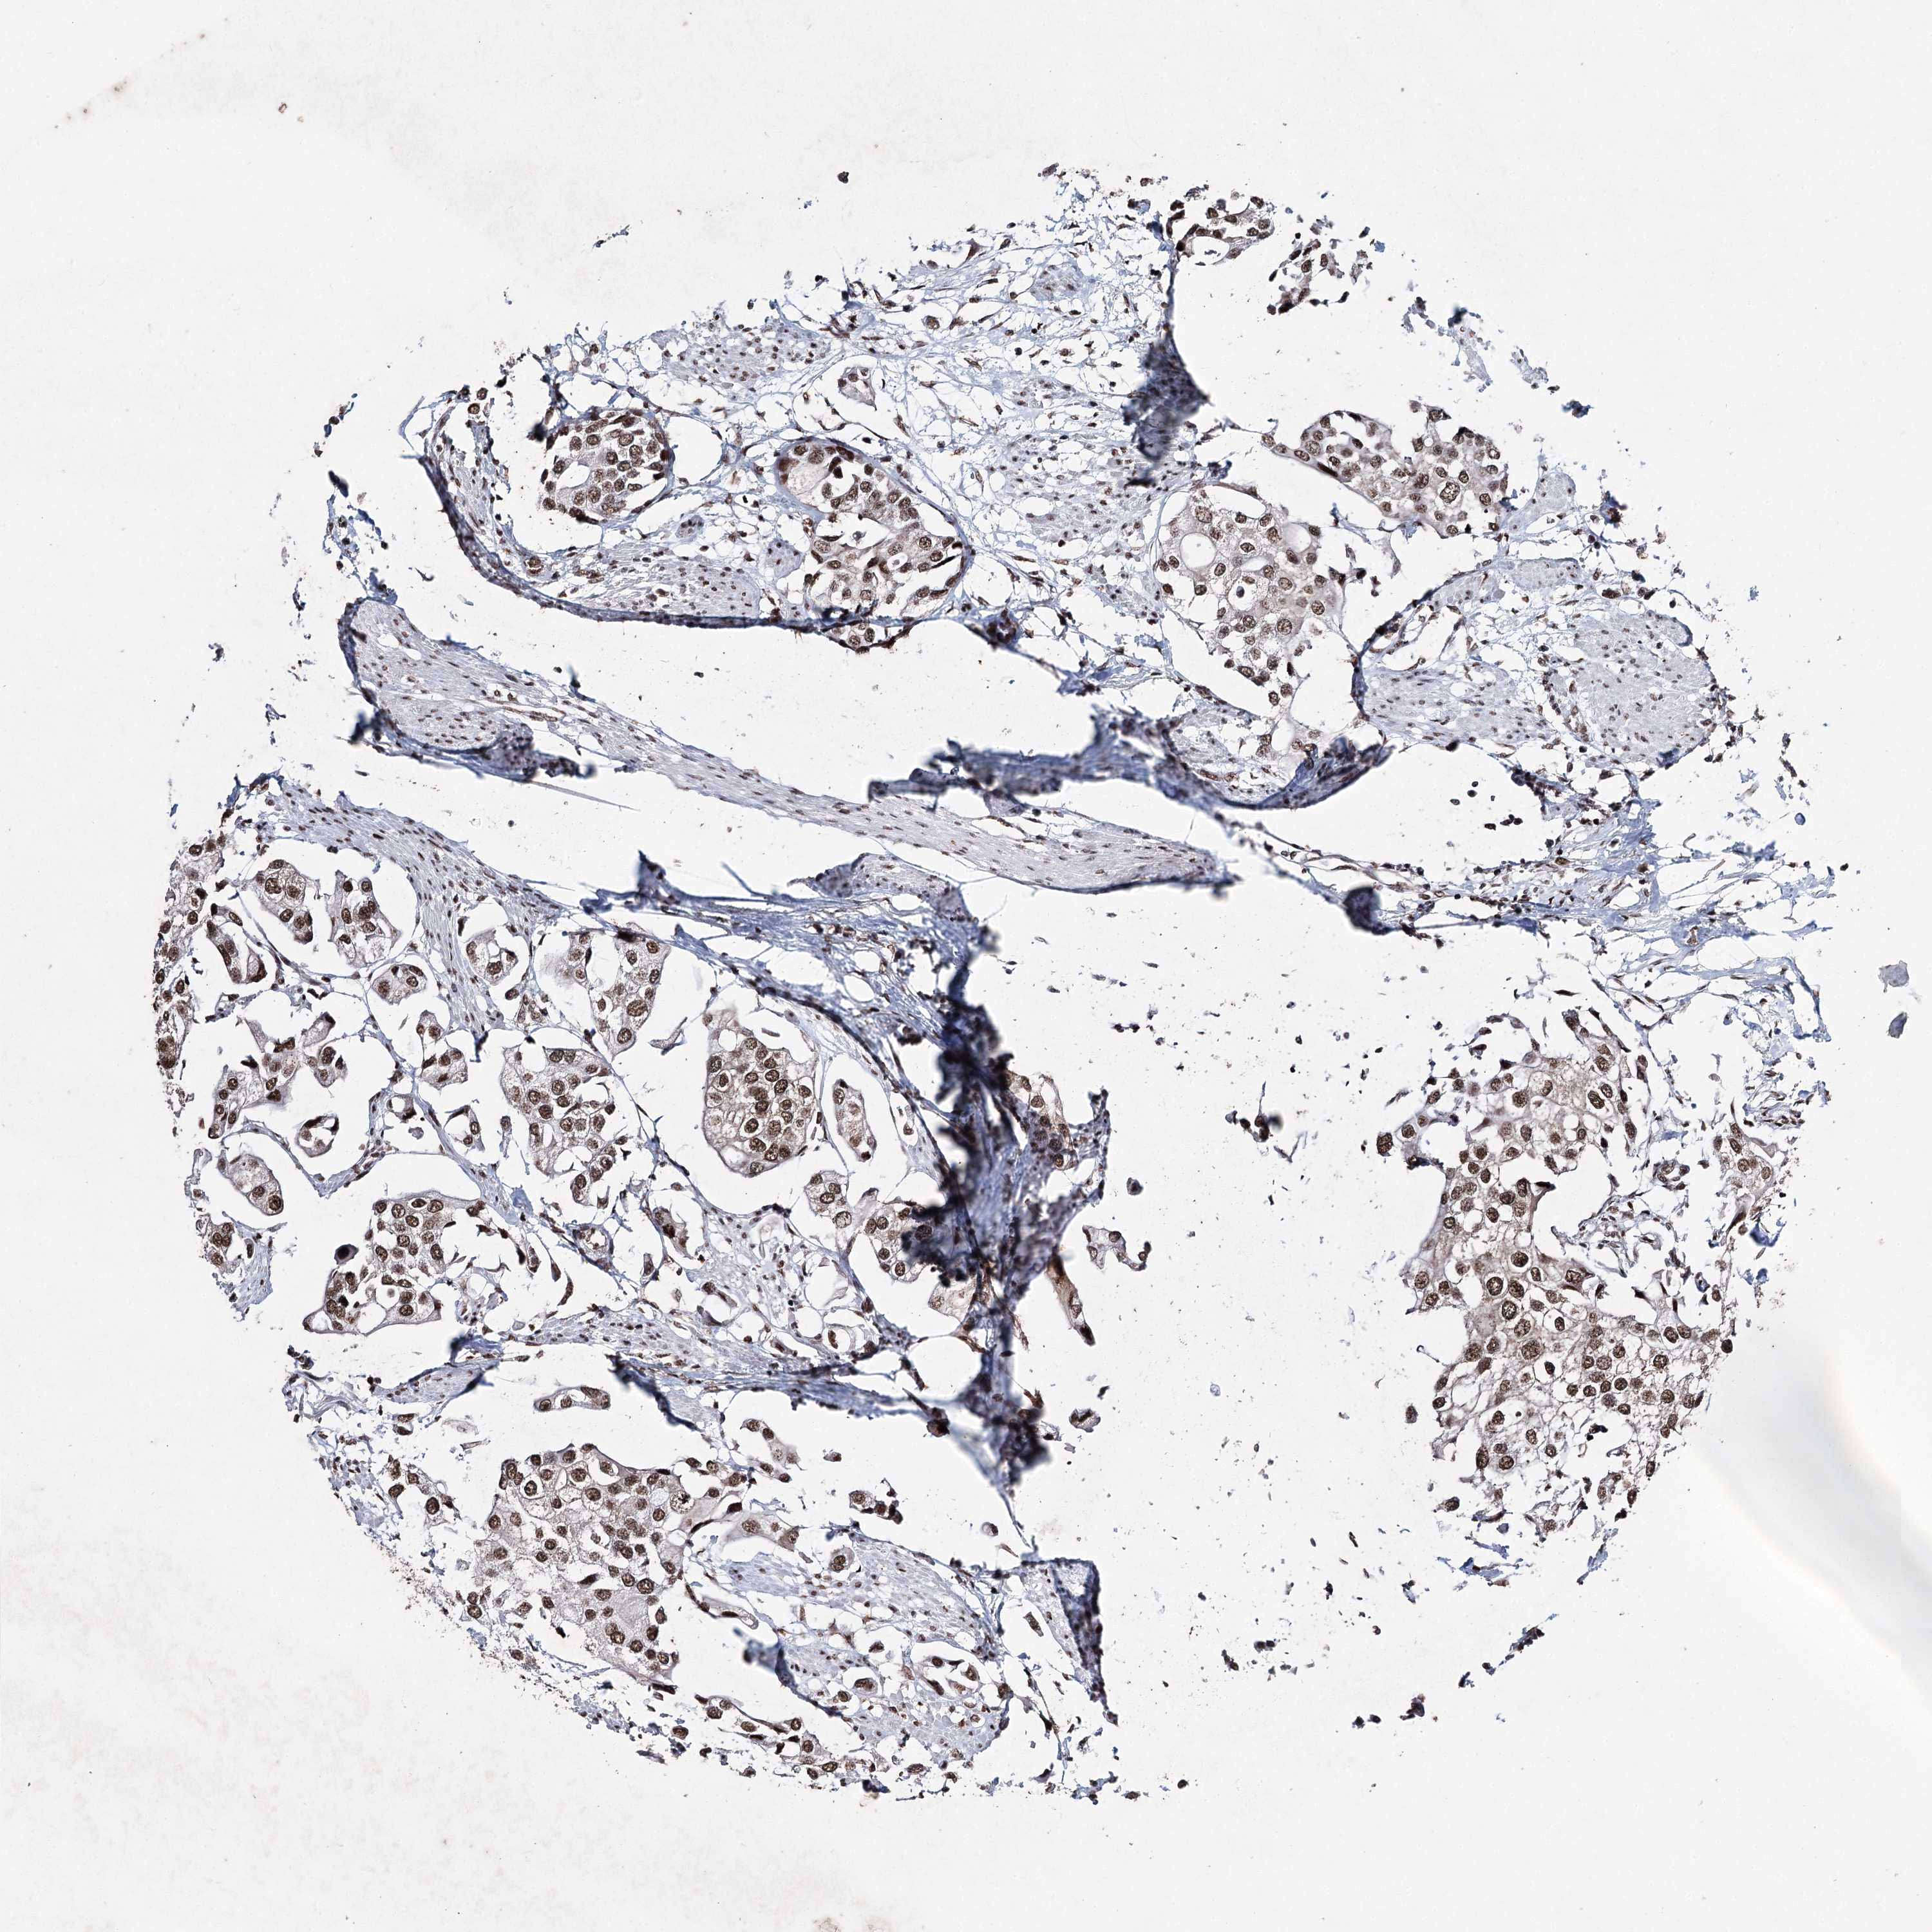

UROTHELIAL CANCER - Protein expressioni

A mouse-over function shows sample information and annotation data. Click on an image to view it in a full screen mode. Samples can be filtered based on level of antibody staining by selecting one or several of the following categories: high, medium, low and not detected. The assay and annotation is described here.

Note that samples used for immunohistochemistry by the Human Protein Atlas do not correspond to samples in the TCGA dataset.

Antibody stainingi

Antibody staining in the annotated cell types in the current human tissue is reported as not detected, low, medium, or high, based on conventional immunohistochemistry profiling in selected tissues. This score is based on the combination of the staining intensity and fraction of stained cells.

Each image is clickable and will lead to virtual microscopy that enables deeper exploration of all samples and also displays staining intensity scores, fraction scores and subcellular localization as well as patient and tissue information for each sample.

Antibody HPA001032

Antibody HPA027214

Antibody CAB037024

Urothelial carcinoma, High grade

Urothelial carcinoma, Low grade

Urothelial carcinoma, NOS